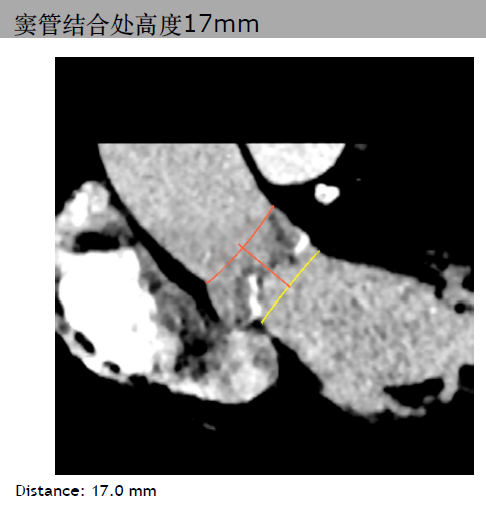

三叶瓣,主动脉瓣环平均直径21.3mm。右冠脉高度10.3mm,右窦直径:28.4mm。左冠脉高度14.1mm,左窦直径:30.4mm。STJ平均直径25.4mm,高度17mm。